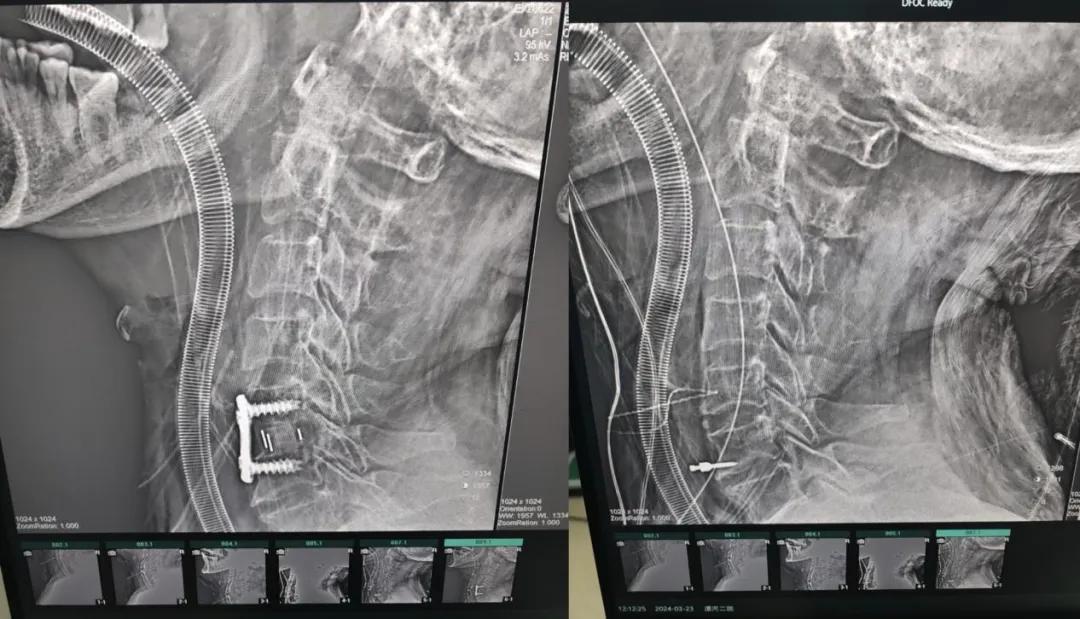

近日,70歲的馬阿姨,因摔傷后出現持續性頸部疼痛伴右側肢體無力、麻痛,影響日常生活。于是來到市二院神經外科就診,經檢查發現:頸椎MR示:頸3/4、4/5、5/6、6/7椎間盤變性突出(中央型)并繼發性椎管變窄,頸椎退行性改變,頸5椎體水平頸髓水腫。神經外科副主任劉沛濤根據患者癥狀、體征、影像學三者結合診斷為“脊髓型頸椎病”,考慮到患者癥狀逐漸加重、保守治療效果不佳等情況,建議盡快手術治療。

經過縝密的術前準備和手術計劃,在鄭大一附院神經外科張風江教授的指導下,神經外科團隊順利為患者實施“顯微鏡下頸椎前路C5/C6椎間盤切除椎間融合+內固定術”,手術時間不到1小時。術后患者恢復情況良好。